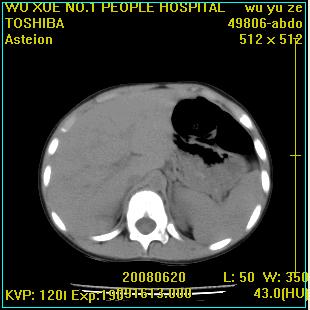

标题: PED0851:患儿,7岁,左腰部外伤一天,伴大量肉眼血尿。 [打印本页]

标题: PED0851:患儿,7岁,左腰部外伤一天,伴大量肉眼血尿。

ct征象与病史不相符,该病变与外伤关系不大,病变相邻组织未见明显外伤性改变,需追问病史及进一步检查

左侧多发肾囊肿,与外伤无关

左肾重度积水,原因不明;不排除左输尿管上段迷走血压迫或先天性狭窄所致可能。

左肾重度积水